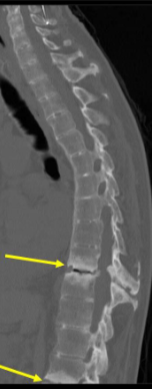

Ankylosing Spondylitis

diagnosis is confirmed by spine radiographs (especially of SI joints)

Bamboo Spine

Minor trauma → vertebral fractures